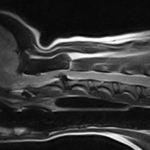

体の何処かを痛がるとの事でダックスさんがかかりつけ医を受診したところ、椎間板ヘルニアではないか?との頃で精査のため来院されました。エックス線検査とMRIでC2~C3に脊髄圧迫病変が確認されました。Ventral Slotで脊柱管内に逸脱した椎間板物質を摘除しました。速やかに除痛効果が現れています。